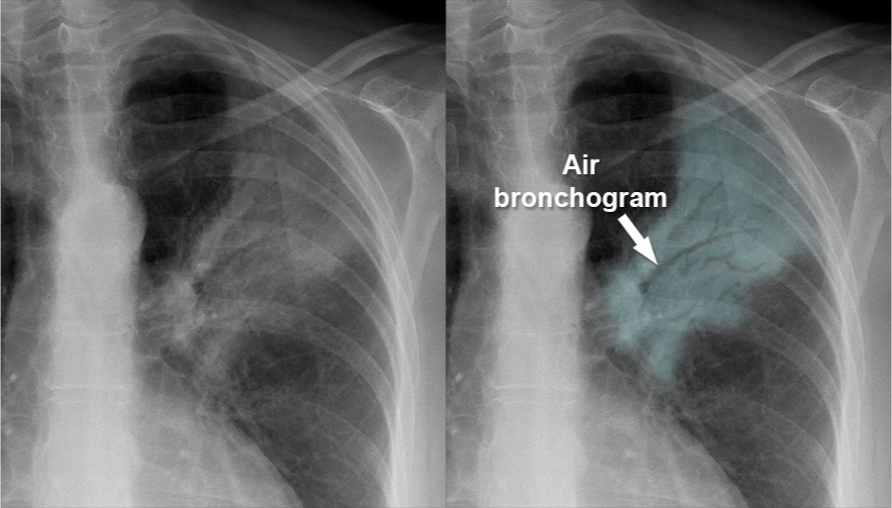

Pattern seen on CXR or CT scans when air-filled bronchi become visible against a background of dense lung tissue.

Air bronchogram sign